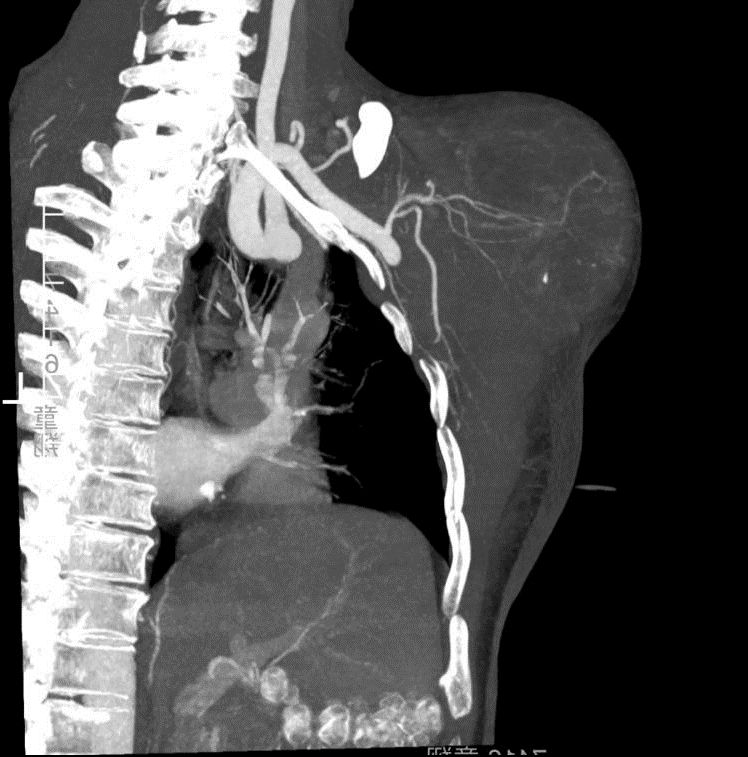

一方面,王哥右肩这个肿瘤包裹从腋窝通往右上肢的血管、神经,稍有不慎就可能造成术中大出血或是伤到神经,那整个右手臂就面临瘫痪甚至坏死的风险;

另一方面,手术前需要更清晰的影像资料来制定手术方案,但王哥每次做磁共振等检查时,都会不由自主地浑身发抖(心理障碍导致),没有办法完成磁共振检查,影像学上根本无法清晰呈现他目前整个右肩关节肿瘤的情况。同时,肿瘤也破坏了肩胛骨的关节盂,侵犯了肱骨近端周围的所有肌腱韧带,就算切除了肿瘤,如何重建一个稳定的肩关节,也是很大的困难。

放射科刘主任带领放射科团队凭借丰富的经验,为王哥尽可能拍到了部分清晰的磁共振影像,为精准制定手术方案奠定了基础。随后,骨科、血管外科、放射科专家团队联合为王哥进行了手术。先堵住那些给肿瘤“输血”的血管,降低术中大出血风险;在肿瘤包裹的最主要动脉血管里植入支架,放置阻断球囊,防止发生大出血,对右手臂的主要动脉进行保护;再剥离、完整切除这个排球大小的肿瘤。 由于肿瘤侵犯了肩关节囊的所有肌肉肩袖组织,王主任将肱骨连同周围的肿瘤组织完整切除,然后用反肩人工假体对王哥的肩关节进行了重建。同时手术室、麻醉科、输血科也对手术的安全顺利完成进行了全力保障。